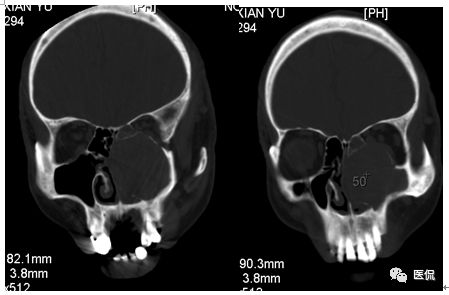

冠状位平扫

CT平扫及增强示:左侧上颌窦及鼻腔可见软组织密度影,呈膨胀性生长,周围骨质压迫性吸收破坏,累及左眶,病灶密度不均匀,周边区可见点状钙化,增动脉期轻度强化,局部见小灶性稍高密度区,静脉期病灶内见不均匀明显强化,CT值最高达117HU,延迟期强化范围有所增大。